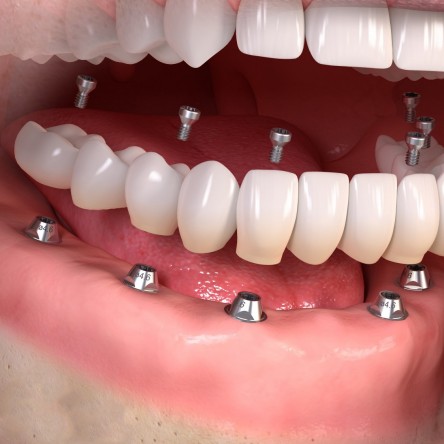

Los implantes como medio para una prótesis

Una vez respetado el período de cicatrización, se llevará a cabo la restauración protética, esto es, conectar el implante osteointegrado a una corona a través de un elemento intermedio conocido como pilar. Este procedimiento puede realizarse de manera atornillada o cementada.

Coronas atornilladas. La fijación de la corona al pilar se lleva a cabo por medio de un tornillo que la atraviesa. El orificio de conexión o “chimenea” será ocultado posteriormente con composite. Importante destacar el riesgo estético inherente asociado a este procedimiento ante la posibilidad de diferencia cromática entre el composite que obtura la chimenea y la cerámica de la corona.

Coronas cementadas. Estéticamente más favorables, la unión de la corona al pilar se realiza por medio de un agente cementante. El riesgo asociado a este procedimiento radica en la dificultad de remoción de los posibles excesos de cemento que pueden causar irritación de los tejidos.

Tipos de rehabilitaciones implanto-soportadas

Cada paciente es único y diferente, por lo que la elección de un tratamiento u otro se verá condicionado por sus características y sus necesidades. En función del número de ausencias dentarias, las opciones terapéuticas varían sensiblemente.

Puente sobre implantes. Cuando al menos son dos los implantes que se utilizan como punto de anclaje para remplazar las ausencias dentarias. El número de implantes que se utilicen como medio de apoyo de la futura prótesis será directamente proporcional a las ausencias dentarias.

Prótesis híbrida. Modalidad FIJA de tratamiento. A diferencia de la anterior, el paciente no podrá retirarla, será el odontólogo el encargado de hacerlo siempre que fuese necesario. Exige un mínimo de 4 hasta un máximo de 6 implantes en la mandíbula y un mínimo de 6 implantes en el maxilar. La prótesis irá directamente atornillada a los pilares, reponiendo la totalidad de los dientes ausentes y mínimamente los tejidos perdidos.

Prótesis fija. Como su propio nombre indica, se trata de una modalidad FIJA de tratamiento. Exige un mínimo de 6 hasta un máximo de 8 implantes en la mandíbula y un mínimo de 6 hasta un máximo de 8 implantes en el maxilar. La prótesis podrá ir atornillada o cementada, reponiendo EXCLUSIVAMENTE la totalidad de los dientes ausentes.